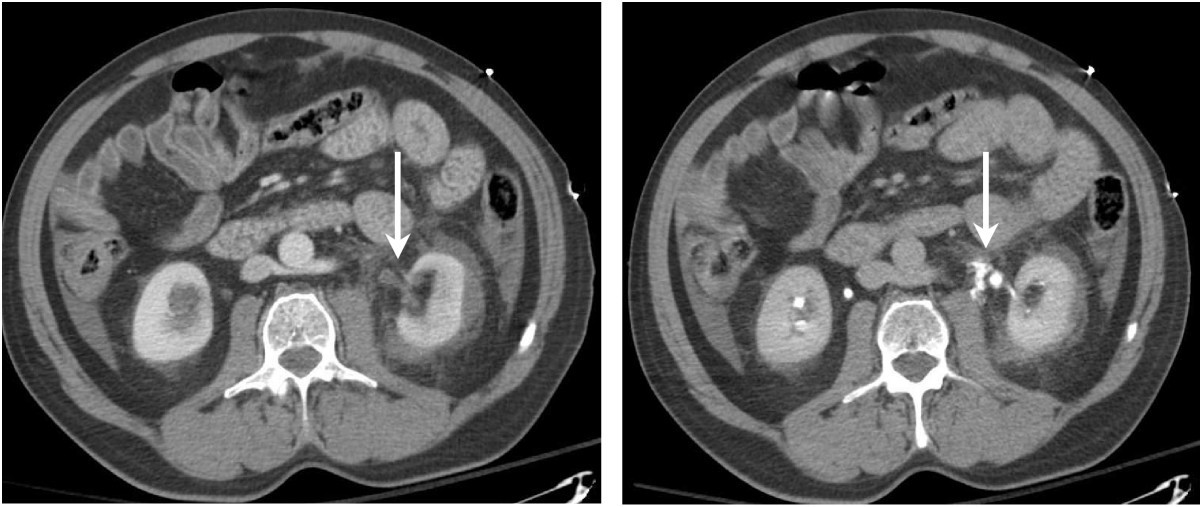

From www.researchgate.net

CT urogram in a 50yearold man with lumbar pain in unenhanced axial Ct Scan Urology It lets your doctor see the size and shape of these structures to determine. You may be offered a ct scan or an mri scan if the specialist feels they need a more detailed picture of your bladder. At these appointments, your bladder will be checked. A ct urogram is used to examine the kidneys, ureters and bladder. The contrast. Ct Scan Urology.